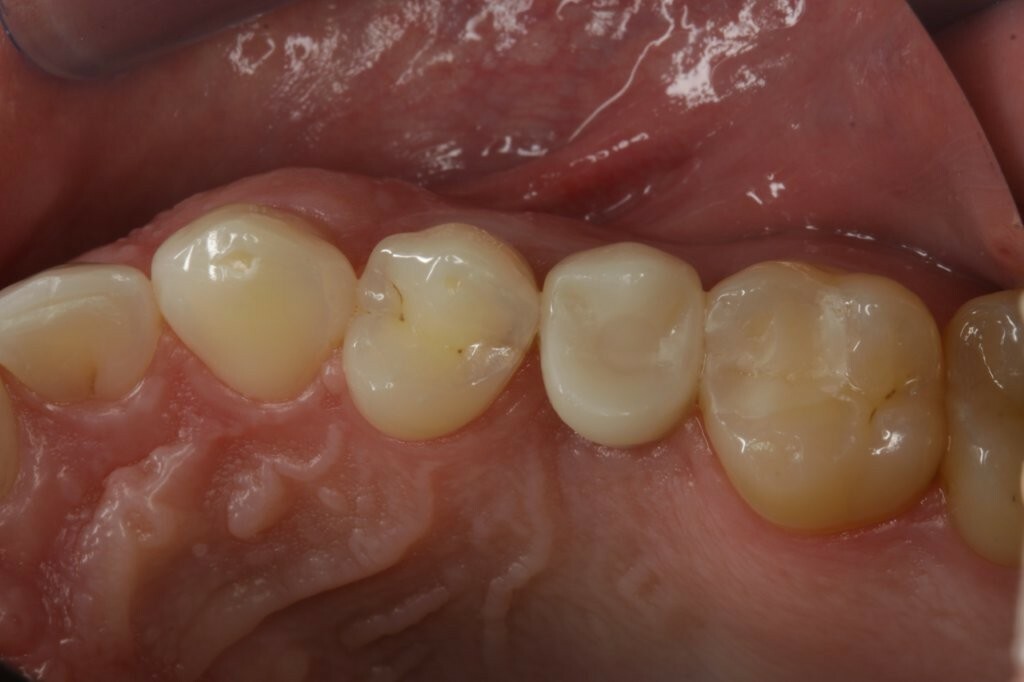

Zu Beginn wurde das Einzelzahnimplantat (Conelog ScrewLine Titanimplantat, 3,8 x 9,0 mm, Camlog) in Regio 25 gesetzt, geschlossen eingeheilt und nach Freilegung mit einem Gingivaformer (Conelog Gingivaformer, wide body, 3,8 x 6,0 mm, Camlog) versehen (Abb. 3). Mithilfe eines VITA-Farbschlüssels (VITA Zahnfabrik) wurde für die spätere Krone die Farbe A3 bestimmt (Abb. 4).

Nach Entfernung des Gingivaformers (Abb. 5) wurde ein Scan-Body (NT-Trading) eingesetzt, um die klinische Situation mit dem Intraoralscanner (Trios3 Move, 3Shape) digital abzubilden (Abb. 6). Die Vollkeramikkrone wurde auf einem gedruckten Arbeitsmodell gefertigt (Abb. 7) und die Okklusion mit Hilfe eines ebenfalls digital erstellten Gegenkiefers im gedruckten Artikulator überprüft (xSNAP, xWERK) (Abb. 8).